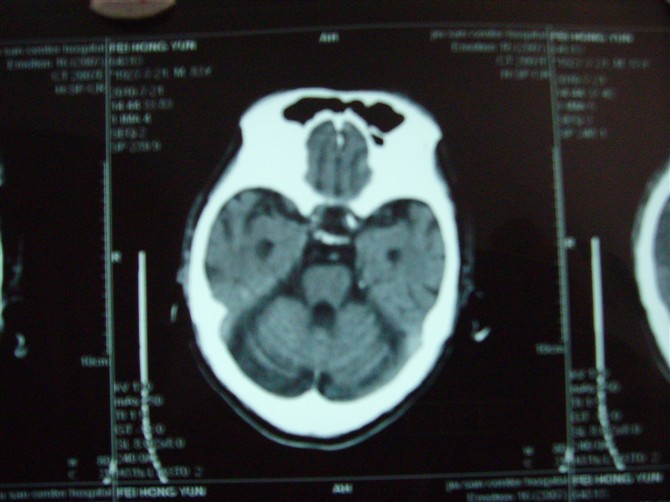

标题: CT27993:男 83岁 头晕伴双下肢无力一天 [打印本页]

标题: CT27993:男 83岁 头晕伴双下肢无力一天

脑萎缩。伴小脑齿状核、苍白球钙化。必要是mri进一步检查。

脑萎缩。伴小脑齿状核、苍白球钙化.脑白质脱髓鞘病变

脑白质变性、脑萎缩。甲状旁腺功能减退。

1)双侧小脑半球脑软化灶。2)全脑萎缩。3)脑白质病。